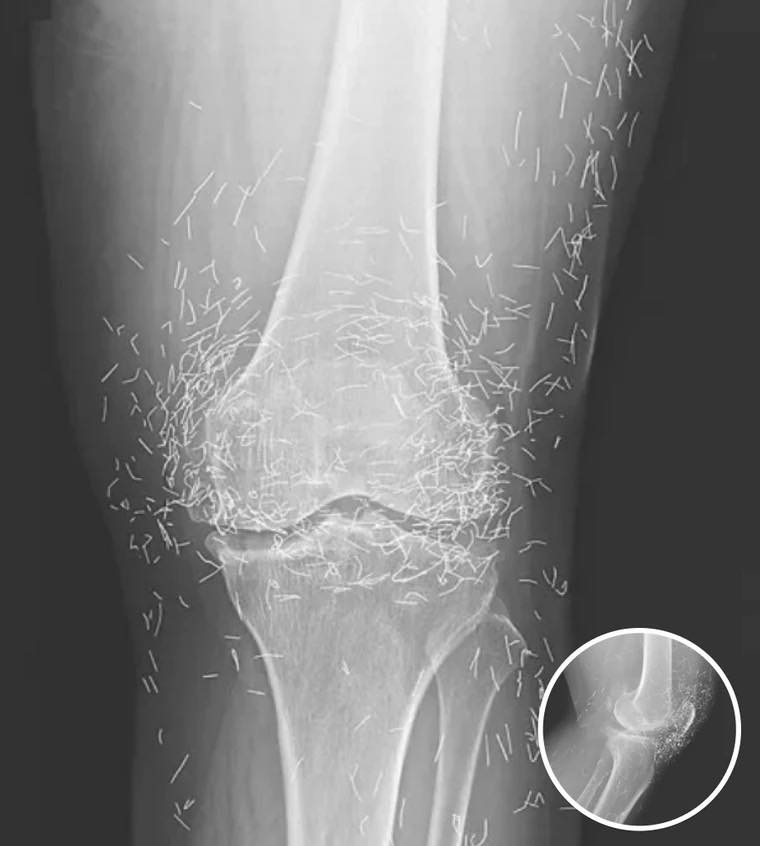

Doctors Stunned After Looking At This X-Ray Of Woman Suffering Joint Pain

A routine X-ray revealed a shocking discovery: hundreds of tiny gold needles embedded in the knees of a 65-year-old woman suffering from severe osteoarthritis. The woman had…